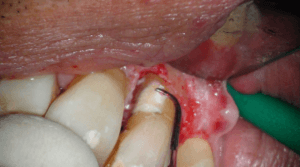

Na anesthesie volgde een flapoperatie om de pocket te openen. Al snel werd een breuk zichtbaar in het element. Maar hoe ver liep de barst door?

Voorzichtig verwijderden we alle granulatieweefsel en spoelden we het schoon. Wat we zagen had ik nog nooit eerder waargenomen. Er zat een min of meer circulaire barst wat eigenlijk een los zittend stukje dentine was.

Na het wegfrezen van het losse stukje vulden we het defect op met composiet. We werken de composiet af met fijne diamantjes en handscalers. Een superscherp geslepen handinstrument kan uitstekend worden gebruikt bij het afwerken van composietvullingen. Wel alleen vlak na het polymeriseren, dan is composiet nog te scalen.